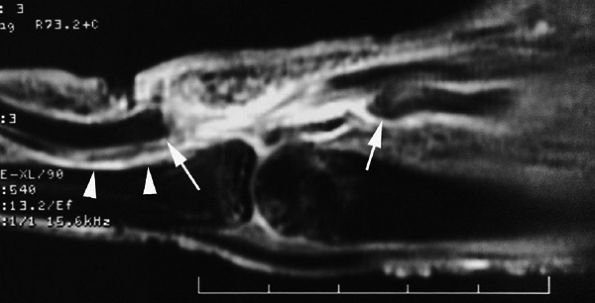

FIGURE 11.55 ● Rupture of A2 pulley of the fourth finger. Sagittal (A) and axial (B) post-contrast T1-weighted images show the tear of the A2 pulley on the midline (black arrowheads) with a palmar dislocation of the flexor tendon. The pulley (white arrow and arrowhead) is now deeply located beneath the flexor tendons. Note the integrity of the A1 pulley (black arrow).